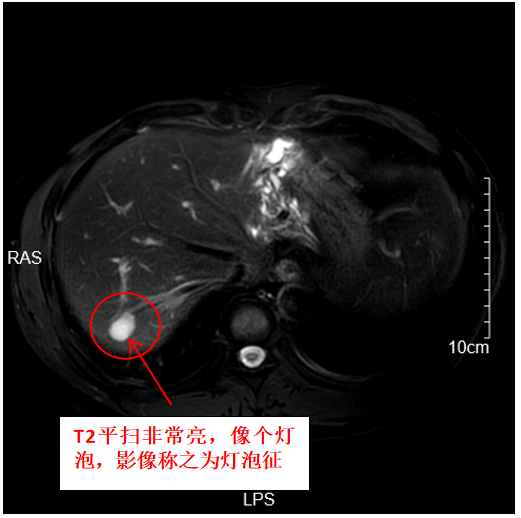

患者體檢查出來(lái)血管瘤很常見,部分患者很緊張,會(huì)糾結(jié)于報(bào)告中的每個(gè)字的描述。以下是一名腸癌患者,肝臟一枚典型血管瘤的CT和MRI表現(xiàn)。接下來(lái)是磁共振MRI表現(xiàn)

劉璐璐醫(yī)生的科普號(hào)2024年08月01日2473

引言隨著人們對(duì)健康的日益關(guān)注和定期體檢意識(shí)的提高,B超因其簡(jiǎn)單、無(wú)創(chuàng)的特點(diǎn)成為了腹部器官常規(guī)體檢的首選檢查手段。這導(dǎo)致越來(lái)越多的人被診斷出肝臟血管瘤。然而,許多人擔(dān)心這是否意味著他們患上了惡性腫瘤。本文將為您揭開肝臟血管瘤的真相。1.血管瘤是腫瘤嗎?血管瘤是一種由肝臟內(nèi)部血管組織異常增生所形成的良性腫瘤。雖然名稱中含有“瘤”,但它通常不會(huì)惡變。2.血管瘤會(huì)惡變嗎?不會(huì)。血管瘤是一種良性病變,不會(huì)轉(zhuǎn)變?yōu)閻盒阅[瘤。3.肝臟血管瘤的B超表現(xiàn)?典型特征:在B超上,血管瘤通常表現(xiàn)為高回聲區(qū),邊界清晰,邊緣規(guī)則。有時(shí)可以看到內(nèi)部或周邊的血流信號(hào)。?非典型表現(xiàn):盡管高回聲是血管瘤的典型表現(xiàn),但也有少數(shù)情況下血管瘤可能呈現(xiàn)為低回聲或混合回聲,這可能與肝臟其他惡性腫瘤如肝細(xì)胞癌的表現(xiàn)重疊。一個(gè)特殊的案例曾經(jīng)有一位40多歲的男性公務(wù)員,在20多年前通過(guò)B超檢查被診斷為肝臟血管瘤。在隨后的20年間,他定期復(fù)查,發(fā)現(xiàn)病灶在緩慢增大,最終甚至達(dá)到了20多厘米。最終,醫(yī)生建議他進(jìn)行磁共振成像(MRI)檢查,結(jié)果發(fā)現(xiàn)這不是血管瘤的典型表現(xiàn),建議手術(shù)切除,最終該患者確診為肝細(xì)胞癌。4.肝臟血管瘤的CT表現(xiàn)?CT平掃:血管瘤在CT平掃中通常表現(xiàn)為低密度灶、低密度結(jié)節(jié)或低密度腫塊,這一表現(xiàn)與肝臟其他惡性腫瘤如肝細(xì)胞癌相似。?CT增強(qiáng):在CT增強(qiáng)掃描中,血管瘤的強(qiáng)化方式通常描述為快進(jìn)慢出、持續(xù)強(qiáng)化、向心性強(qiáng)化或漸近性強(qiáng)化,但這些表現(xiàn)也可能與肝臟其他惡性腫瘤如肝內(nèi)膽管癌的表現(xiàn)重疊。5.肝臟血管瘤的MRI表現(xiàn)?T2加權(quán)像:在MRIT2加權(quán)像上,血管瘤通常呈明顯高信號(hào),像燈泡一樣亮,被稱為“燈泡征”。?擴(kuò)散加權(quán)成像(DWI)及ADC圖:在DWI及ADC圖上,血管瘤通常呈明顯高信號(hào)或描述為擴(kuò)散不受限。?增強(qiáng)掃描:增強(qiáng)掃描同樣顯示為快進(jìn)慢出、持續(xù)強(qiáng)化、向心性強(qiáng)化或漸近性強(qiáng)化。綜合各個(gè)序列表現(xiàn),基本能準(zhǔn)確診斷出血管瘤。6.是否需要使用肝臟特異性對(duì)比劑普美顯??結(jié)論:不需要。無(wú)論是血管瘤還是肝細(xì)胞癌,在使用普美顯增強(qiáng)掃描后均呈現(xiàn)為低信號(hào),因?yàn)檫@些病變都不是正常的肝細(xì)胞,因此使用普美顯對(duì)血管瘤的診斷沒(méi)有附加意義。7.血管瘤需要治療嗎??小病灶:對(duì)于直徑小于5厘米的血管瘤,通常建議定期復(fù)查為主。?大病灶或有癥狀:對(duì)于直徑大于5厘米的血管瘤或出現(xiàn)臨床癥狀的血管瘤,可以考慮手術(shù)或影像引導(dǎo)下的介入治療。8.結(jié)論如果您被診斷為肝臟血管瘤,請(qǐng)不要過(guò)度擔(dān)憂。大多數(shù)情況下,定期復(fù)查就足夠了。當(dāng)懷疑是血管瘤時(shí),可以行MRI增強(qiáng)掃描輔助診斷。了解血管瘤的真實(shí)面貌,有助于我們更加理性地面對(duì)這一情況。。